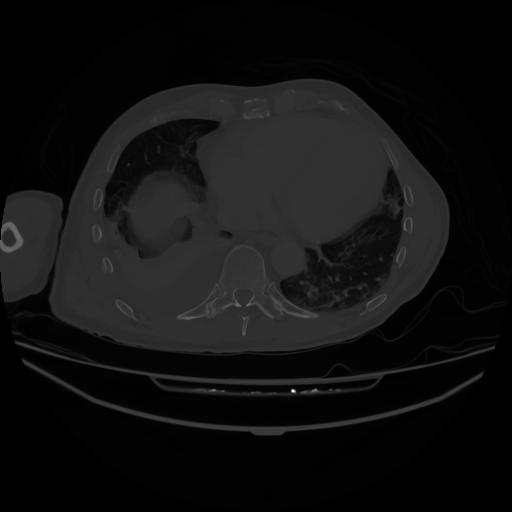

5 CUERPO,CE,Vol,1.0,CUERPO,,